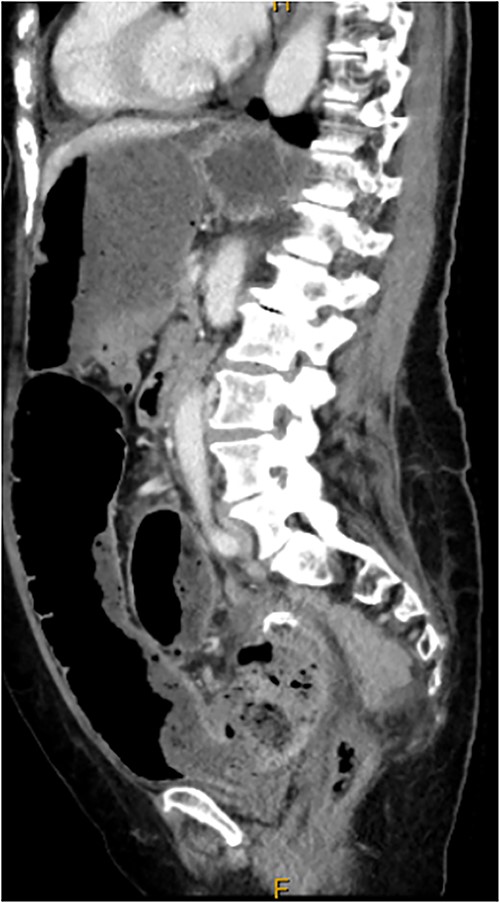

Computed tomography on current presentation demonstrated a mechanical LBO with a transition point at the anastomosis, with significant large bowel dilatation (see Figs 1 and 2). Flexible sigmoidoscopy revealed severe luminal narrowing at the anastomosis 20 cm from the anal verge prohibiting scope progression, with intra-luminal purulent discharge. She underwent a laparotomy and Hartmann’s procedure, with findings of severe colorectal anastomotic stenosis and a small, localized perforation. The colon proximal to the stricture was dilated but viable, with a caecal diameter of approximately 20 cm (see Figs 3 and 4). Histopathology confirmed a benign stricture with extensive fibrosis and a segment of full thickness necrosis and perforation. There was no evidence of malignancy and the post-operative recovery was unremarkable.

CT scan demonstrating dilatated proximal large bowel and caecum (arrow).